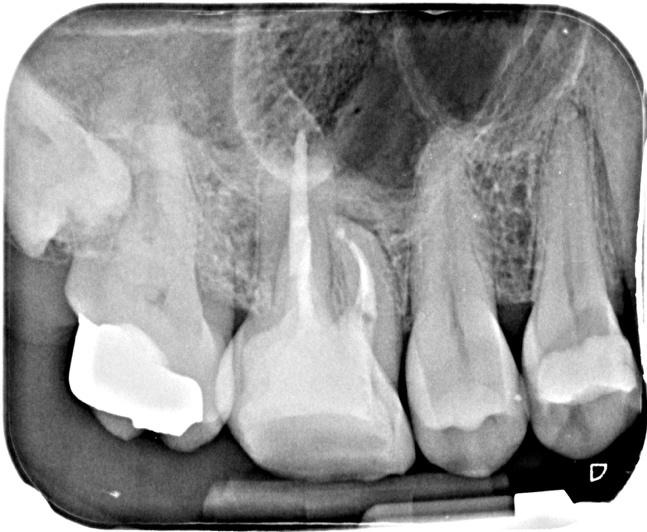

Post-op IOPA’s

As a result, the cracks were not deemed detrimental to the treatment outcome but were included in the patient’s consent and also highlighted the need for cuspal coverage straight after re-treatment in order to protect the tooth. A pre-endo build-up in 3M’s Filtek Bulk One composite helped seal these cracks beforehand. The re-root treatment was then completed using Reciproc Blue R25, VDW Rotate 2504 for the mb2 and R40 for the wider palatal canal. Following copious irrigation and lots of activation, the canals were obturated using a combination of a squirt fill technique with Totalfill BC sealer Hiflow to try and negotiate the 2-1-2 configuration apically in the mesial root and CWC in the other roots. Patency was not achieved in the palatal root. However, due to the absence of any obvious inflammatory change attached to this root on the pre-op CBCT scan it is less likely to affect the outcome of this case. This patient was then returned to their RD for cuspal coverage without delay!

I have suggested a follow up CBCT scan in 12 months’ time to assess healing in 3D, especially as this case had been diagnosed and planned in 3D. I’ll add this to the case once I have it.